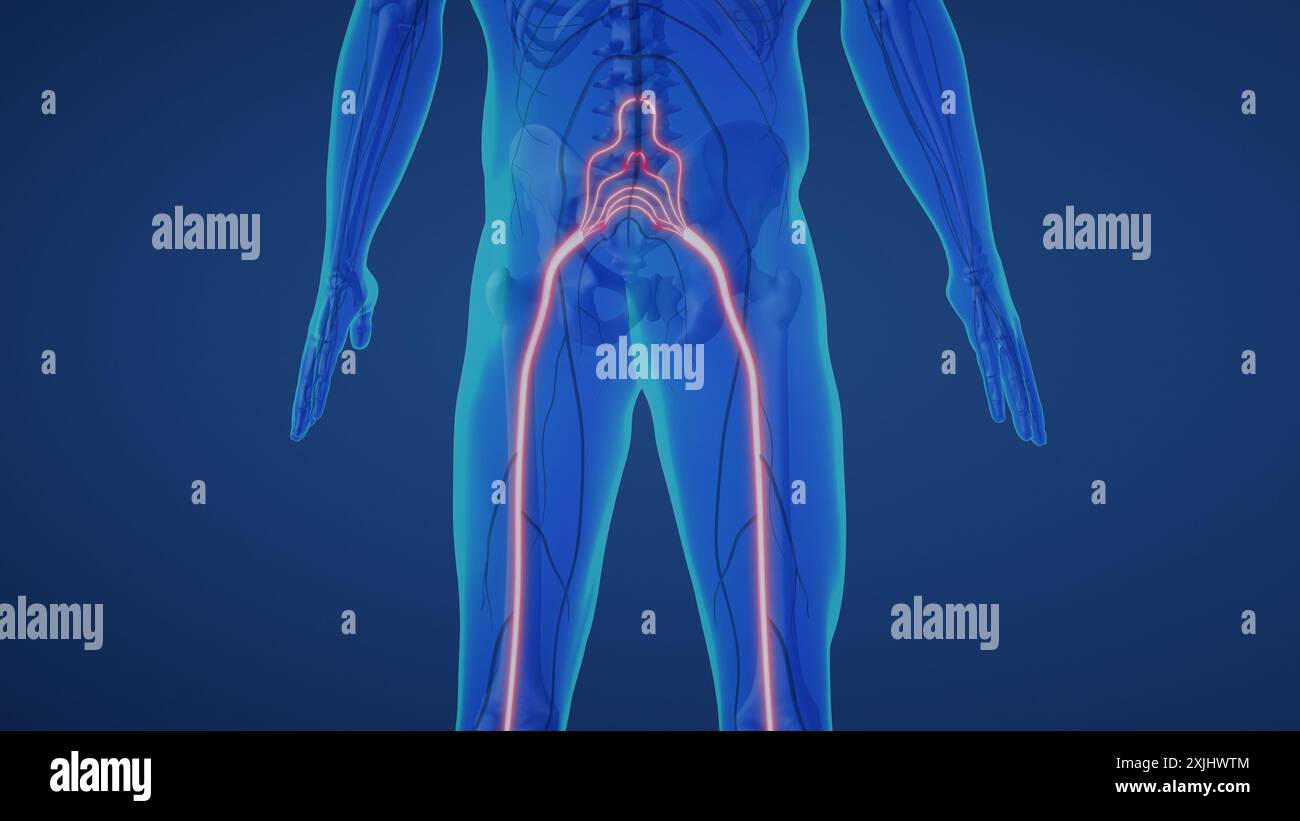

Nervenschmerzen des Ischias im Unterkörper Stockfotohttps://www.alamy.de/image-license-details/?v=1https://www.alamy.de/nervenschmerzen-des-ischias-im-unterkorper-image613820164.html

Nervenschmerzen des Ischias im Unterkörper Stockfotohttps://www.alamy.de/image-license-details/?v=1https://www.alamy.de/nervenschmerzen-des-ischias-im-unterkorper-image613820164.htmlRF2XJHWTM–Nervenschmerzen des Ischias im Unterkörper